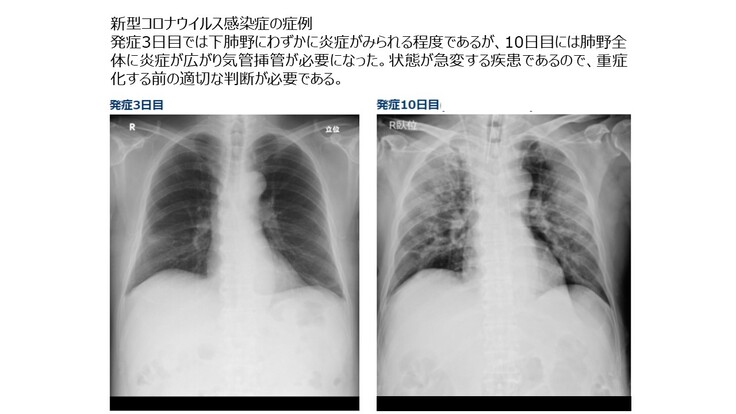

●新型コロナウイルス感染症でも画像診断が重要

新型コロナウイルス感染症の重症化を防ぐためには正確な画像診断が必要です。新型コロナウイルスによる感染はPCR検査で検出できると一般には考えられていますが、PCR検査での検出精度は70%程度と言われており、PCR検査が陰性でも感染している症例は数多く存在します。また正確な診断が間に合わず自宅やホテルでの療養中に死亡する例も多数発生しています。

そこでWHOでは新型コロナウイルス感染症の診断に対して画像診断を利用するようにアドバイスを行っています。(胸部画像診断の COVID-19 への適用:緊急アドバイスガイド)

新型コロナウイルスによる感染拡大が一段落しても、季節性インフルエンザのように人類は新型コロナウイルスと共存することが必要となります。したがってWHOがアドバイスを行っているように入院前に一般のかかりつけ医などが画像診断を行い、専用病棟への入院の必要性などを判断するケースが想定されます。